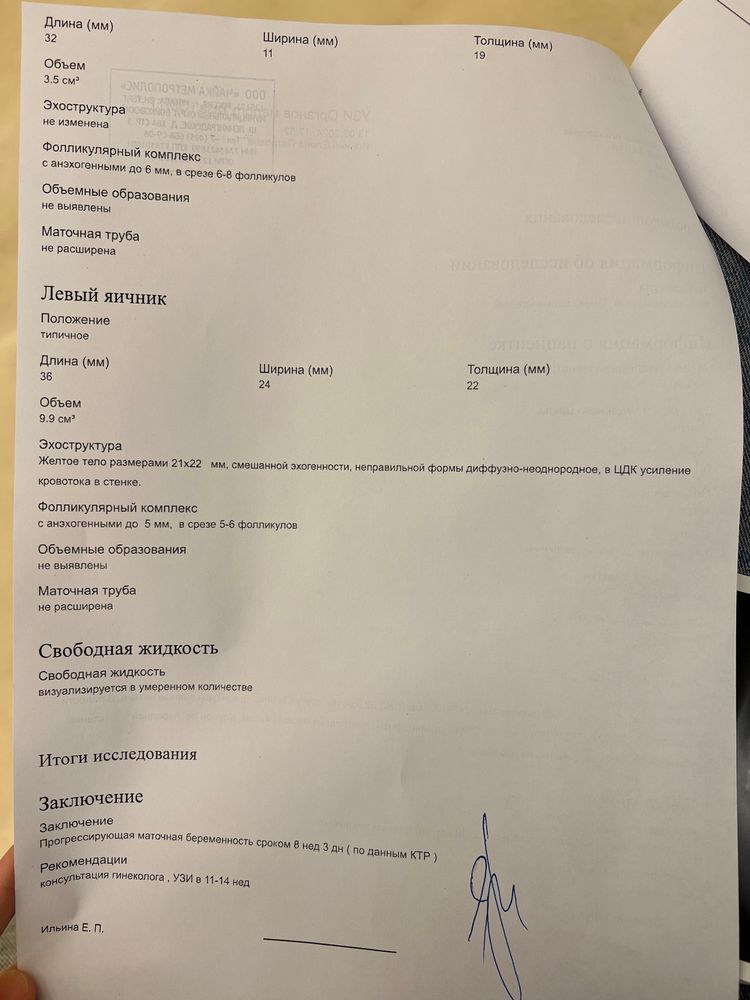

Здравствуйте! Дорогие дамы, прикрепляю 2 узи от 13.02.2024 и от 24.02.2024. Нормально малыш вырос? Узистка странно написала на первом узи, что малыш по ктр на 8 недель и 3 дня, хотя аппарат показывал 8 недель ровно. Сегодня у меня (24.02.2024) 10 недель ровно, а аппарат показал 9 недель и 4 дня. На самом первом узи в 6 недель и 3 дня мне аппарат показывал, что малыш по размерам на 6 недель ровно. То есть, везде стабильно 3 дня разница с акушерским сроком. Сегодня аппарат показал ЧСС 177, но узистка написала в протоколе 171, почему-то.